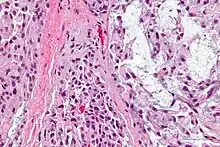

| Micrograph of a myoepithelioma. H&E stain. | |

Pathology

The myoepithelial cells may be spindled, plasmacytoid, eithelioid or clear. Tubules or epithelium are absent, or present in a small amount (<5%) by definition. Tumours with myoepithelial cells and a large amount of tubules are classified as pleomorphic adenomas (which must also contain the characteristic chondromyxoid stroma, which is normally absent in myoepithelioma).

Myoepitheliomas are diagnosed from an examination of the tissue by a pathologist.